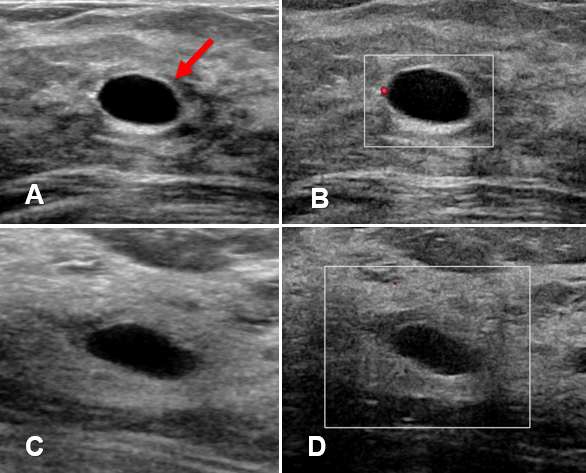

Case: Cysts figure 2

Figure 2A and 2B show CC and MLO views (respectively) of a right breast with a well circumscribed, oval, low-density mass in the right breast at 6 o’clock, middle depth. Background fibroglandular elements are visualized through the mass without evidence of calcifications or architectural distortion.